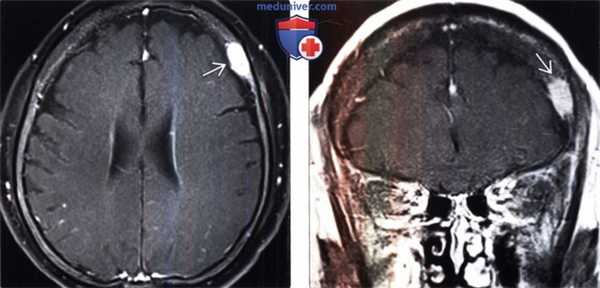

(Слева) Одиночные метастазы свода черепа часто хорошо визуализируются на Т1 -ВИ без подавления сигнала от жира, поскольку опухоль замещает желтый костный мозг в диплоэтическом пространстве.

(Справа) МРТ, Т2-ВИ, аксиальный срез: у этой же пациентки наблюдается, что поражение имеет смешанный изо-/гиперинтенсивный сигнал по отношению к смежному нормальному диплоэтическому пространству.

(Слева) МРТ, постконтрастное Т1 -ВИ, режим подавления сигнала от жира, аксиальный срез: у этой же пациентки отчетливо определяется поражение свода черепа.

(Справа) МРТ, постконтрастное Т1 -ВИ, корональный срез: определяется легкая неровность контуров поражения. Несмотря на то, что поражение и пенетрирует внутреннюю компактную пластинку черепа, признаков вовлечения в процесс нижележащей твердой мозговой оболочки не наблюдается. Данное поражение было единственным метастазом известного рака молочной железы.